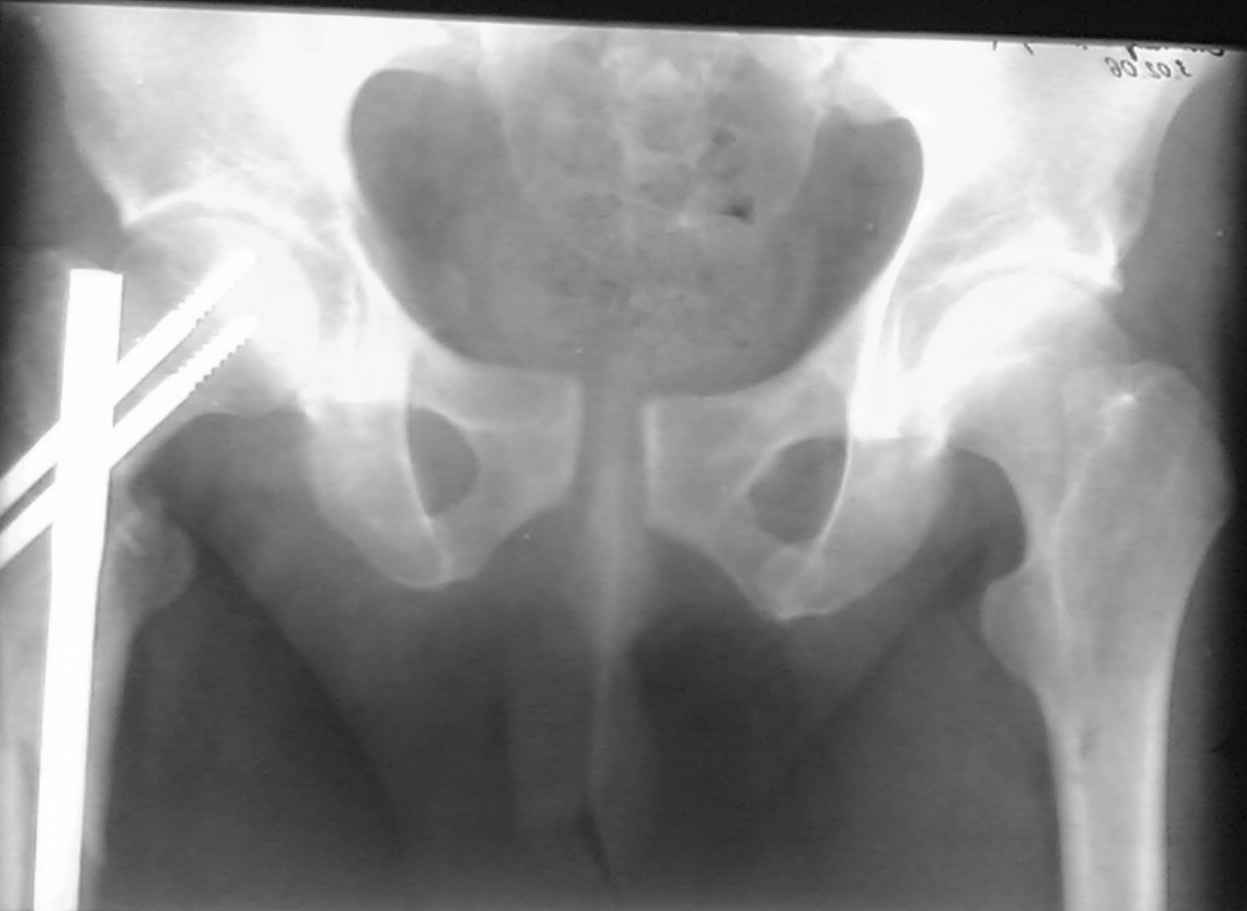

ПЕРЕСМАТРИВАЛ РАЗНЫЕ СНИМКИ И НАШЕЛ НА ЭТУ ТЕМУ ФОРУМА СНИМОК. БОЛЬНОЙ БЫЛ ПРООПЕРИРОВАН НА ПРАВОЕ БЕДРО ПОСЛЕ ЧЕГО СДЕЛАН ТАЗ В ЦЕЛОМ. ВОТ ЧТО НАШЛОСЬ.

КАКОЕ ВАШЕ МНЕНИЕ О ТАКТИКЕ.

ДУМАЮ ПРОШЛО ОКОЛО 10 ДНЕЙ.

В представленном случае повреждение несомненно ротационное и реальный диастаз как раз около пограничных 2,5 см, репозиция идеальная, достигнута в первые дни после травмы. Я бы ограничился 3 мес фиксации в аппарате с ограничением нагрузки первый месяц, и функциональными снимками в 6 -8 недель.